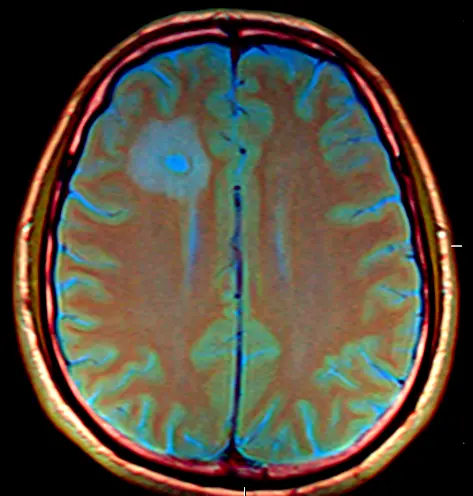

Tumorabsiedlungen im Gehirn sind schwer, schlimmstenfalls gar nicht zu bekämpfen: Sie lassen sich oftmals nur schlecht operieren, klassische Chemotherapien scheitern in der Regel, Bestrahlung schädigt auch das gesunde Gehirn. Neun Forschungsgruppen aus ganz Deutschland haben daher nun ein gemeinsames, von der Deutschen Krebshilfe gefördertes Verbundprojekt gestartet, um Strategien gegen die Neubildung der gefährlichen Hirnmetastasen zu entwickeln.

Viele Krebsarten können Absiedlungen im Gehirn bilden, am häufigsten jedoch schwarzer Hautkrebs, bestimmte Formen des Brustkrebs und Lungentumoren. Bei rund der Hälfte der Patienten, die an diesen Krebsarten sterben, entwickeln sich im Erkrankungsverlauf Gehirnmetastasen. Chemotherapien, welche die Tumoren im restlichen Körper schädigen und erfolgreich bekämpfen, erreichen die Zellen im hermetisch abgeschirmten Gehirn nicht – die Medikamente können die sogenannte Blut-Hirn-Schranke, mit der das Gehirn gegen im Körper zirkulierende Gifte und Krankheitserreger geschützt ist, nur schlecht durchdringen. Dazu kommt noch eine weitere Schwierigkeit: Neue Erkenntnisse aus der Forschung weisen darauf hin, dass sich Hirnmetastasen in ihrer Biologie grundsätzlich von Tumorabsiedlungen in anderen Organen unterscheiden. Medikamente, die gegen die Metastasenneubildung eingesetzt werden, wirken daher im Tierversuch fundamental anders als gegen große Tumoren. Gängige Krebsmedikamente würden daher, selbst wenn sie ins Gehirn eindringen könnten, meist nicht helfen.

Darüber hinaus weiß man derzeit noch wenig darüber, wie die Tumorzellen es überhaupt schaffen, in das Gehirn gelangen und es zu besiedeln. Das Team von Frank Winkler, Arbeitsgruppenleiter in der Kooperationseinheit Neuroonkologie der Neurologischen Universitätsklinik und des Deutschen Krebsforschungszentrums, war vor einigen Jahren daran beteiligt, einige generelle Abläufe zu klären: Krebszellen, die sich vom ursprünglichen Tumor gelöst haben und in die Blutbahn gelangt sind, quetschen sich durch die Wand der Blutgefäße im Gehirn und bleiben außen an diesen hängen. In diesen „Gefäß-Nischen“ finden sie offenbar ideale Bedingungen und wachsen zu neuen Tumoren heran.